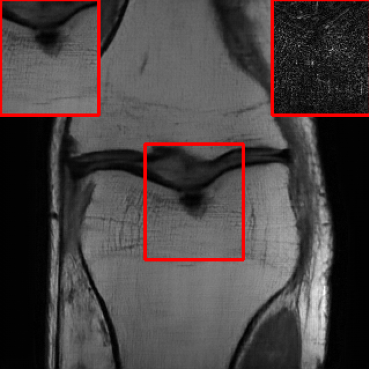

Performance on the Stanford FSE Dataset: We also performed image reconstructions with the Stanford multi-coil FSE dataset, which is a smaller dataset. We used same settings for the networks and training as in Section IV-A. Table III shows that LONDN-MRI significantly outperforms the globally learned MoDL network at both 4x and 8x acceleration. This indicates benefits for the proposed framework for smaller, more diverse datasets. Figs. 7 and 8 display visual comparisons that show the LONDN-MRI scheme recovering sharper features than the globally learned network.

| Ground Truth | Initial | Global | LONDN-MRI | LONDN-MRI | Oracle |

| (1 iteration) | (2 iterations) | ||||

![]() |

| PSNR = dB | PSNR = 22.01 dB | PSNR = 29.02 dB | PSNR = 31.46 dB | PSNR = 31.74 dB | PSNR = 31.87 dB |